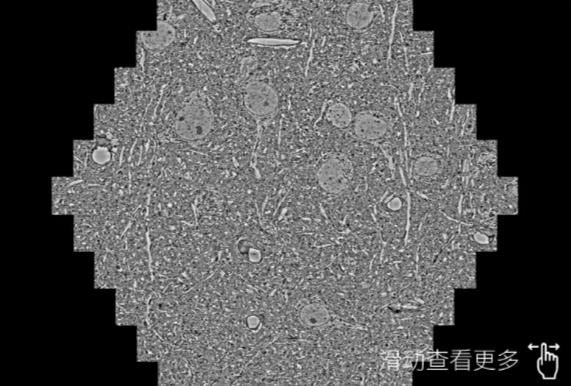

鼠脑切片。左图使用合川蔡司合川扫描电镜MultiSEM706对165μmx143pm面积区域成像,耗时仅需1.5秒。右图为鼠脑切片中30μm区域放大效果。样品由芝加哥大学B.Kasthuri提供。

使用蔡司高速合川扫描电镜MultiSEM对1mm²人脑皮层组织进行高分辨成像,并对其中的各种细胞结构进行三维重构分析。左图展示了2x3mm²组织平面中锥体神经元的三维重构效果。右图显示了局部体积神经元三维重构。图像由哈佛大学chtman实验室提供,渲染图由D. Berger 制作。